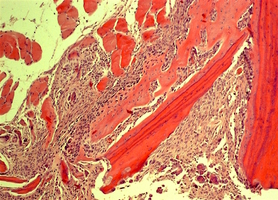

Биоимплантаты аллогенные стерильные губчатые механически и и ультразвуком обработанные.

Часть (фрагмент) костной ткани человека. Костный препарат натурального кадаверного (трупного) происхождения, аллогенный материал.

Фрагмент правильной формы неоднородной поверхности без дополнительных включений и субстанций натурального или синтетического происхождения.

По внешнему виду представляет собой пористый губчатый блок номинального размера.

2. Поверхность и структура материала для изготовления биоимплантатов